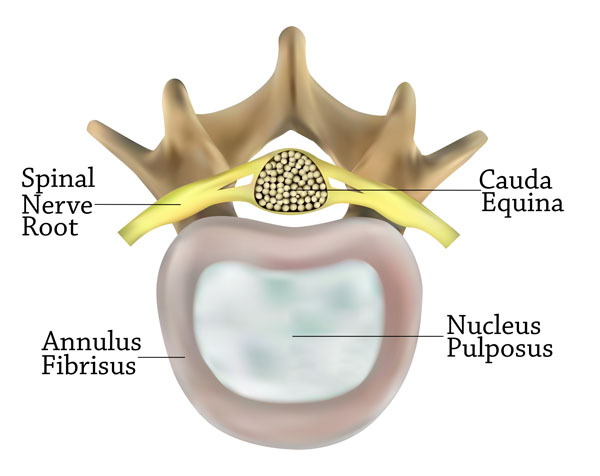

The image presents an axial view of a vertebra at the level where the spinal nerve root exits the vertebral column. It offers a closer look at the structures within and surrounding the vertebra.

Central to the image is the vertebral body, which is the large, oval-shaped structure providing the majority of the vertebra’s weight-bearing capability. Within the vertebral body, we see the nucleus pulposus, represented in a lighter shade, which is the inner core of the intervertebral disc. This gel-like substance allows the disc to absorb shock and provides the flexibility necessary for the spine’s movement.

Surrounding the nucleus pulposus is the annulus fibrosus, depicted as a thick ring. This is the tough, outer layer of the intervertebral disc, consisting of several layers of fibrocartilage. It contains the nucleus pulposus and distributes pressure evenly across the disc.

Above the vertebral body, the spinal nerve root is shown in yellow, exiting the vertebral column. This nerve root is part of the peripheral nervous system and carries motor, sensory, and autonomic signals between the spinal cord and the body.

Behind the spinal nerve root, the image labels the cauda equina, a bundle of spinal nerves and spinal nerve rootlets. Named for its resemblance to a horse’s tail, the cauda equina continues from the termination of the spinal cord down within the lumbar and sacral vertebral levels.

This image encapsulates crucial components of vertebral and neuroanatomy, emphasizing the relationships between the spinal cord, nerve roots, and the supportive structures of the intervertebral discs.